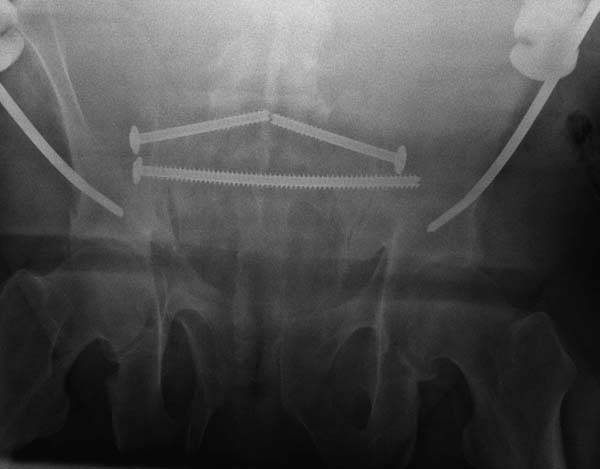

Двухстороннее повреждение крестца и травматическая ампутация бедра, где

неопытной бригадой дежурантов установлен верхний наружный фиксатор для

стабилизации. На третий день ревизия на более стабильный, и

окончательная фиксация. Первые снимки после стабилизации таза, и другие,

где показаны (параллельные) правильная установка на AIIS т.е на месте

прикрепления прямой мышцы бедра. Ампутация закончена костно пластическим

методом.